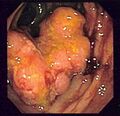

Endoscopic image of colon cancer identified in sigmoid colon on screening colonoscopy in the setting of Crohn's disease